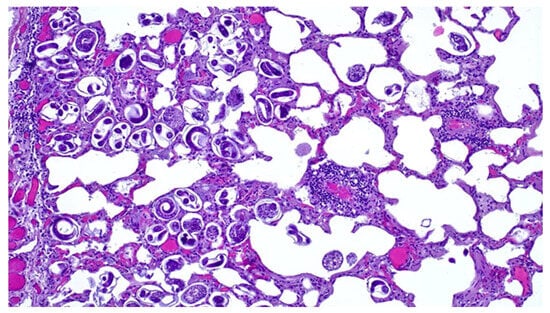

3.3. Microscopic Lesions

Microscopically lung tissue showed a severe parasitic infestation with numerous nematode larvae and eggs present in various stages of development in the bronchioles and the alveolar lumen (Figure 3), consistent with a parasitic bronchopneumonia. A multifocal mild thickening of the alveolar septa, due to the infiltration of macrophages; eosinophils; granulocytes and lymphocytes; hyperemia; the perivascular infiltration of lymphocytes; and peribronchial lymphoid hyperplasia were also observed. Mediastinal lymph nodes showed follicular hyperplasia and the slight infiltration of eosinophil and neutrophil granulocytes, while lymphoid hyperplasia of the splenic white pulp and liver congestion were also observed.

Figure 3. Lung. Histological section. Note the eggs of pulmonary nematodes in various stages of development and first-stage larvae. H&E stain (20×).

Bacterial pulmonary pathology associated with C. pseudotuberculosis is exacerbated by verminous bronchopneumonia related to the presence of high numbers of nematode eggs and larvae, which is particularly severe in the caudal lobes. Several studies have reported a prevalence of Dictyocaulus spp. in the lungs of roe deer in fairly similar climatic areas [,,]. Although the pathogenic significance of nematode infestation in wild ruminants is still controversial, some authors have hypothesized that susceptibility to infestation is closely linked to the poor condition of the animal [], so we could assume that the severity of parasitic pneumonia is related to, or perhaps a contributing cause of, the severely compromised health status of the animal, creating conditions for bacterial dissemination.